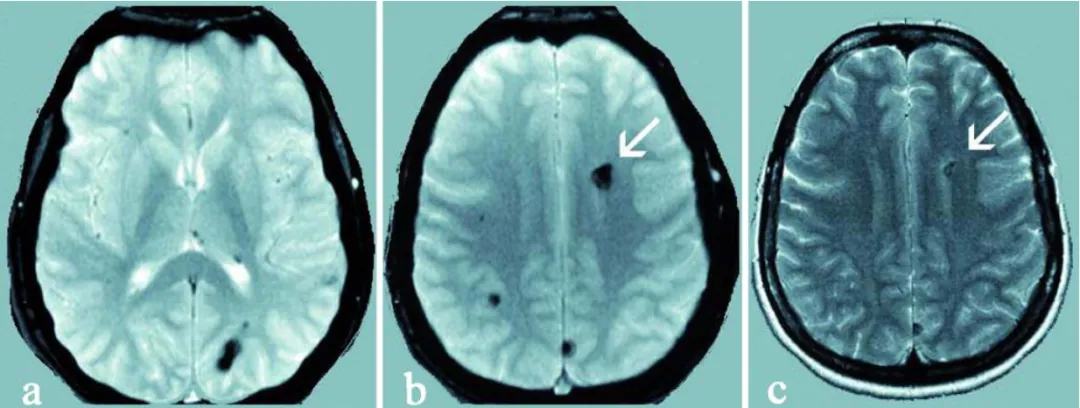

a、b :27 岁母亲的梯度回波磁共振扫描可见多发幕上海绵状血管瘤,呈典型低信号。

c 该无症状母亲的常规 T2 加权磁共振扫描可见左侧额叶最大的海绵状血管瘤(白色箭头所示)。